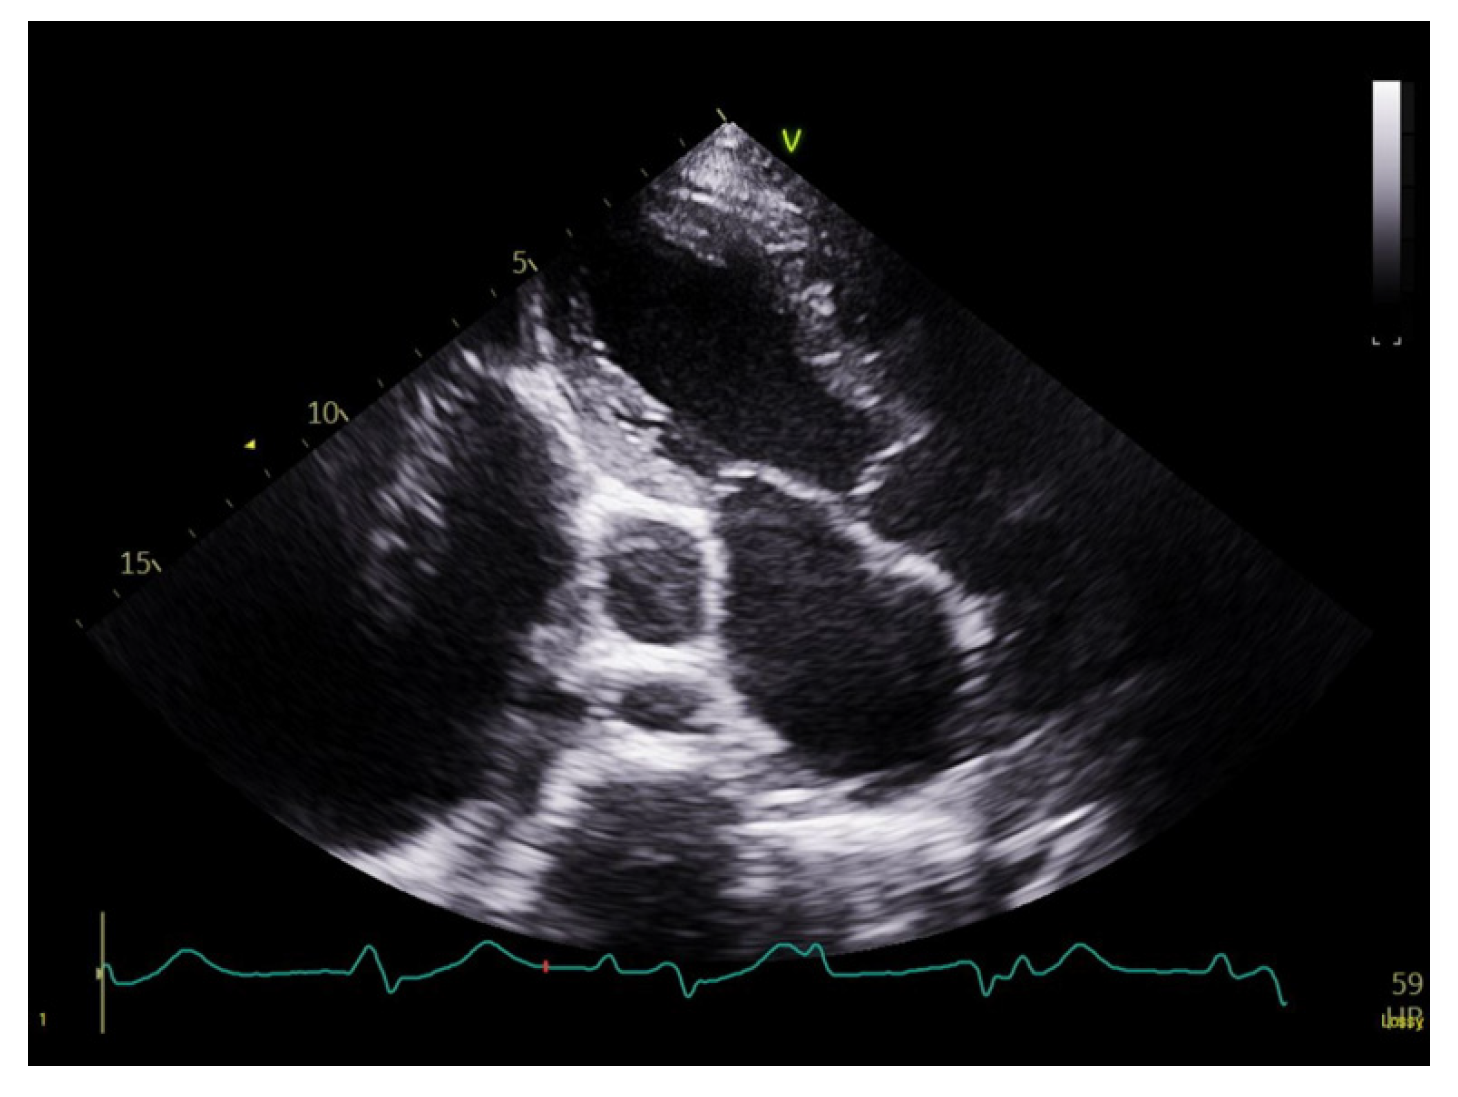

Subsequently, the patient developed oxygen desaturation, prompting a contrast-enhanced chest computed tomography (CT) scan. The scan revealed bilateral pleural effusions, significant CS dilation associated with a PLSVC, cardiomegaly, and biatrial enlargement (Fig. 4). The pleural effusion was successfully drained using a pigtail catheter.

Figure 4: Coronal contrast-enhanced chest computed tomography showing severe dilation of the coronary sinus secondary to persistent left superior vena cava, with marked biatrial enlargement, cardiomegaly, and bilateral pleural effusions.